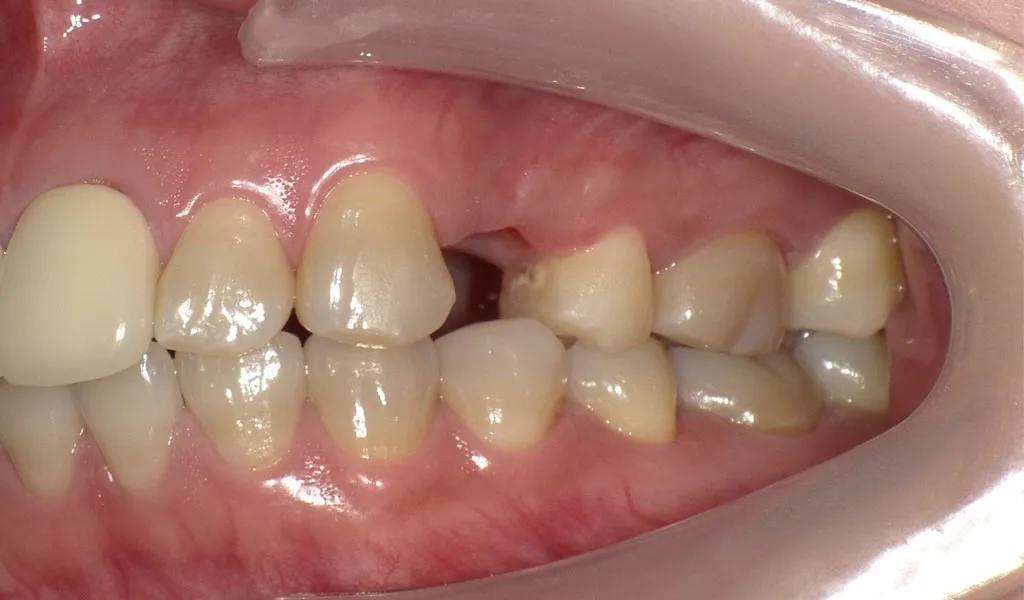

Before

After

奥歯2本のインプラント治療

30代女性

治療期間:4ヶ月

費用:総額64.9万円(検査・診断・手術関連処置費用等を含む)

リスク:出血、腫脹、疼痛、神経麻痺、補綴物の脱落、破折、インプラント体の破折、咬合違和感、インプラント周囲炎など -